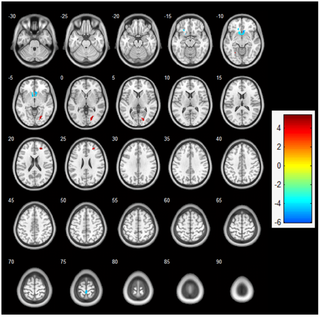

El ejercicio aeróbico agudo aumenta la actividad cortical durante la memoria de trabajo: un estudio de resonancia magnética funcional en estudiantes universitarias

Efectos del Ejercicio Aeróbico Agudo en la Actividad Cortical y la Memoria de Trabajo en Mujeres...